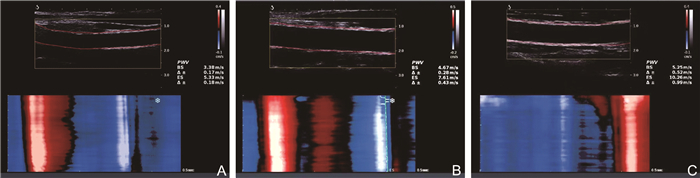

极速脉搏波技术在系统性红斑狼疮亚临床动脉粥样硬化中的评估价值及其临床相关因素研究

王星, 陆芳, 石彦, 李阳, 谢长好

2025, 23(7): 1192-1195. doi: 10.16766/j.cnki.issn.1674-4152.004095

325 2

摘要:

目的  应用极速脉搏波技术评估不同活动度系统性红斑狼疮(SLE)患者的血管弹性并探究其相关危险因素。  方法  选取2020年10月—2024年4月就诊于蚌埠医科大学第一附属医院的116例SLE患者,根据SLE疾病活动性指数2000分为轻度活动组(57例)和中重度活动组(59例),纳入45名健康成年人作为对照组。测量各组的颈动脉内中膜厚度(IMT)、收缩期起始时的脉搏波传导速度(PWV-BS)及收缩期末的脉搏波传导速度(PWV-ES),比较3组颈动脉参数及临床资料,分析脉搏波传导速度(PWV)与各指标之间的相关性。  结果  3组间PWV-BS、PWV-ES比较,中重度活动组>轻度活动组>对照组(P<0.05)。PWV-BS与颈总动脉IMT(r=0.315, P < 0.001)、收缩压(r=0.190, P=0.041)、舒张压(r=0.191, P=0.040)呈正相关关系,PWV-ES与颈动脉分叉处IMT(r=0.274, P=0.003)、颈总动脉IMT(r=0.361, P < 0.001)、舒张压(r=0.252, P=0.006)呈正相关关系。  结论  SLE患者的颈动脉弹性减低明显早于健康者,极速脉搏波可定量评估SLE患者颈动脉弹性,且不受限于时期,这为临床早期动脉硬化评估提供了客观依据。